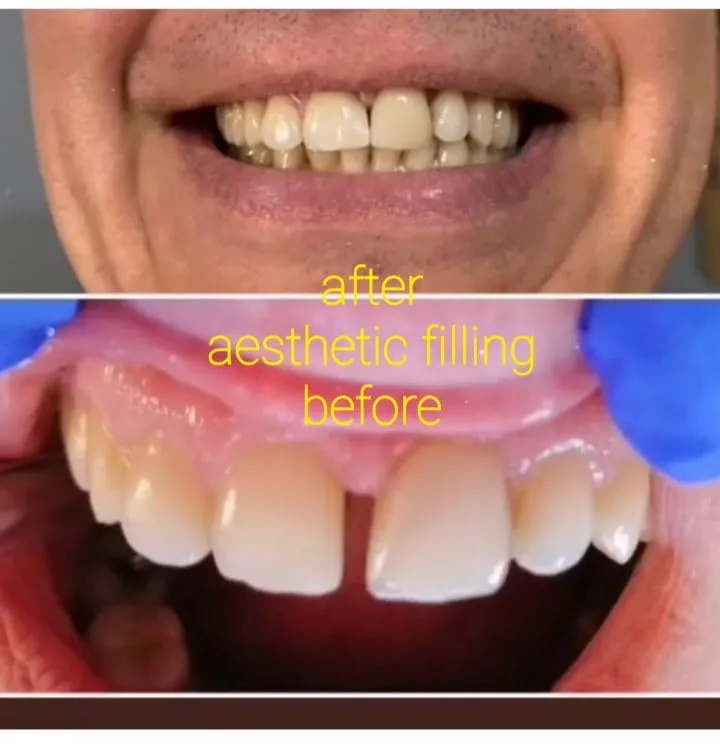

✅ Ästhetische Zahnheilkunde: Aufhellung und Restauration